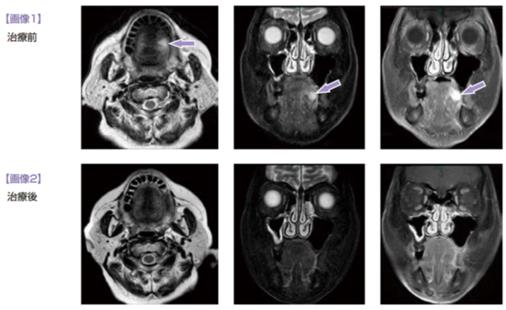

免疫细胞疗法之舌癌

83岁女性,2011年2月因舌左侧糜烂赴综合医院就诊,诊断舌鳞癌cT2, cN0, cM0, cStⅡ。标准疗法... -